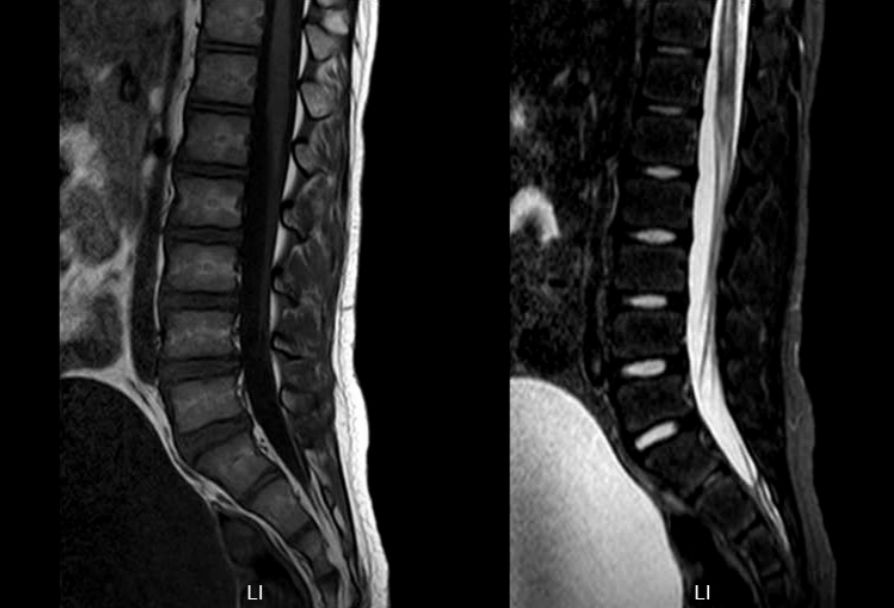

头颅MR:左侧小脑半球异常信号,左侧脑室体部后外侧异常信号,双侧半卵圆中心、侧脑室旁血管周围间隙增多。颈胸髓及腰骶部MRI提示:C3-T4平面脊髓肿胀,伴多发异常信号,胸髓全段肿胀,伴信号异常,腰骶髓异常信号影,考虑脊髓炎可能(图1)。

图1. 第一次住院头颅及脊髓MRI,显示左侧小脑半球异常信号。脊髓全段肿胀,伴信号异常,腰骶髓异常信号影,考虑脊髓炎可能。